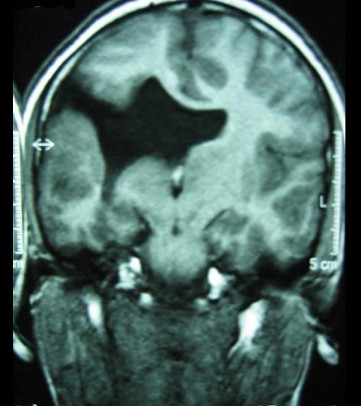

9岁男孩,有癫痫发作史,MR表现如图,首先考虑以下哪个疾病 ( ) TLC-00501.jpg TLC-00502.jpg TLC-00503.jpg TLC-00504.jpg

• A.胼胝体发育不全

• B.脑灰质异位

• C.Dandy-Walker综合征

• D.脑裂畸形

• E.无脑回畸形